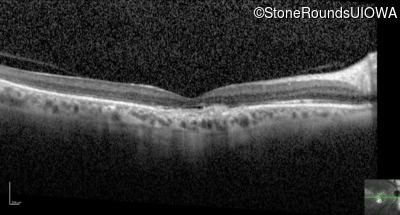

Optical Coherence Tomography - Right - 20/125 -2

Exemplar / OCT Stack

OCT Stack